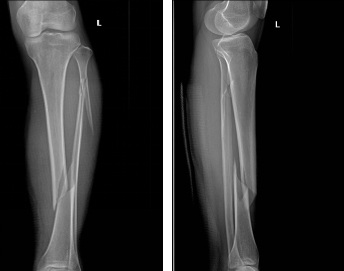

患者李某,女,40岁,因跌倒致左小腿疼痛、活动受限伴流血1小时余于入院,入院诊断:左胫腓骨骨折,患者X线提示:左腓骨上段、左胫骨中下段骨折。骨折移位明显,断端呈螺旋型,骨折不稳定,有手术指征,在我院行左胫骨骨折切开复位+钢板螺钉内固定术。

术前X线示: